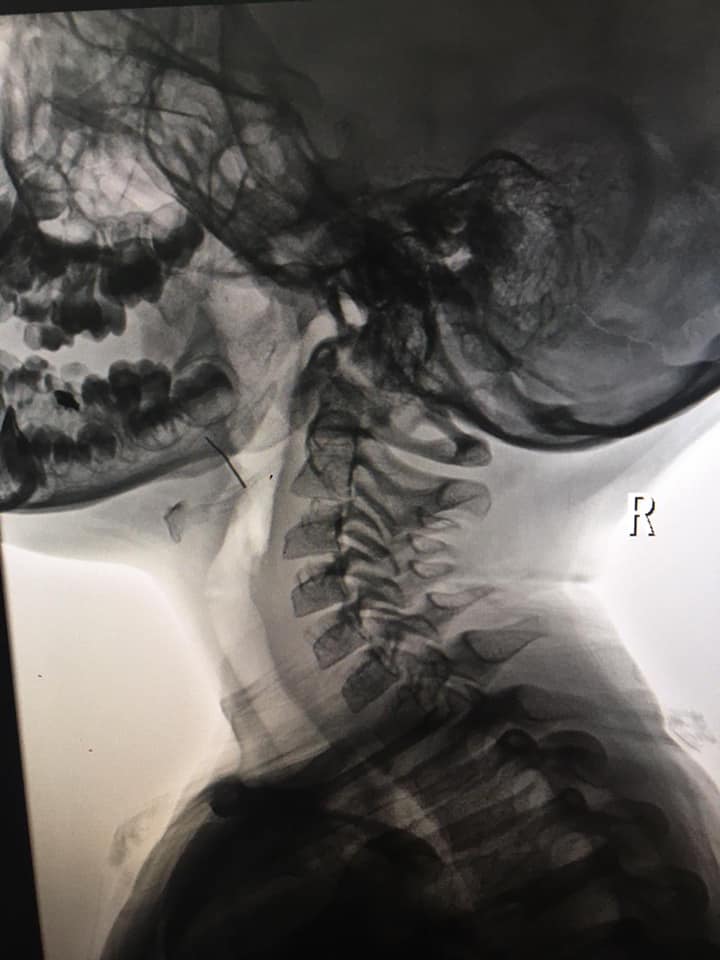

«Семирічна дівчинка з Дрогобича потрапила до нас за скеруванням від районного ЛОРа. Нашому завідувачу ЛОР-відділення Федору Юрочку передали рентген-знімки дитини. Сумнівів не було – у горлі дитини чітко видно стороннє тіло!

“Наші анестезіологи виконали дитині наркоз за особливою методикою, який дозволяє оперувати без застосування ендотрахеальної трубки. У такий спосіб діставати сторонній предмет з горла набагато легше. Працювали ендоскопом. При дуже ретельному огляді ми побачили у тканині кореня язикового мигдалика дротик. Видно, мама пробувала його дістати, але її зусилля дали зворотній ефект – дротик зайшов ще глибше у тканини. Нам вдалося забрати його щипцями, обійшлися без розтинів тканин. Довжина його – приблизно 2 сантиметри”, – розповів Федір Юрочко», – зазначається у дописі.